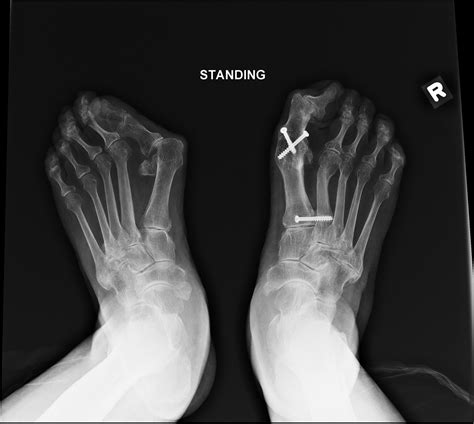

Diagnosing problems with the 1st MTP joint typically involves a combination of physical examination, medical history, and imaging tests. A healthcare professional will assess the joint's range of motion, tenderness, and any visible deformities. Imaging tests such as X-rays, MRI, or CT scans may be used to get a clearer picture of the joint's structure and identify any underlying issues.

Imaging tests provide detailed views of the joint and surrounding structures. X-rays can show bone abnormalities, while MRI and CT scans offer more detailed images of soft tissues, ligaments, and tendons.

When conservative treatments fail to provide relief, surgical intervention may be necessary. The type of surgery depends on the specific condition and the extent of the damage. Common surgical procedures for 1st MTP joint issues include:

• Osteotomy: Realigning the bones to correct deformities and improve joint function.

• Arthrodesis: Fusing the joint to eliminate pain and improve stability, although this limits mobility.